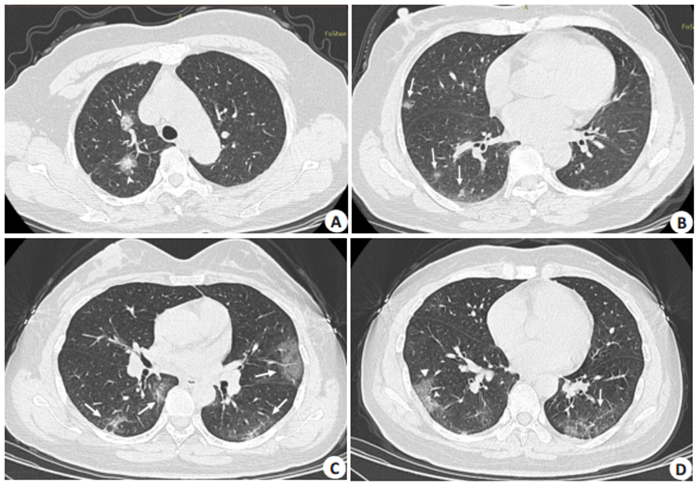

2.2 CT表现9例COVID-19中,共有76个病灶,多数位于胸膜下(67个,88.2%),少数位于肺中内带(9个,11.8%);7例患者CT表现为双肺多发病灶,多位于肺外周或胸膜下,不按肺叶或肺段分布,下肺多见;呈斑片状、团片状、扇形磨玻璃影,常合并肺血管增粗和微血管增多、小叶间隔增厚及纤维化,内衬网格样、如小气泡样,呈“铺路石征”改变(3例);2例随着病情进展,累及多个肺叶并相融合,病灶范围扩大、密度增高,呈不规则形、楔形或伞形,呈双侧非对称性分布。9例COVID-19中,均有“蒲公英果实征”,共46个病灶(33/55,60.5%),其表现为“蒲公英果实绒团征”(9个,19.6%,8个位于胸膜下)与“蒲公英种子征”(37个,80.4%,均位于胸膜下)(图 2)。(9例COVID-19的CT特征如表 1所示)。

图 2 NCP患者CT图像 Fig.2 Chest CT images of 2 patients with SARS-CoV-2-associated pneumonia. A, B: Bilateral subpleural multiple ground glass opacity with solid components (arrows) and "dandelion clew-like" sign (arrows in A) in a 58-year-old female patient. C, D: Bilateral subpleural multiple ground glass opacity (arrows) and dandelion seed sign (triangle) in a 48-year-old female patient (arrows indicate the pulmonary vessels). |